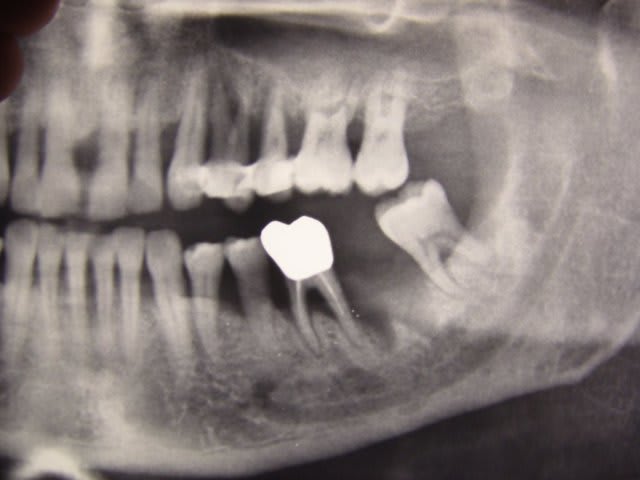

D'après l'hémi-radio, le père de ton pote semble avoir des dents plutôt indemnes de caries et de soins, son extraction est donc due à de sérieux pbs paro (abcès, mobilité)à priori.

La perte osseuse est généralisée mais plus sévère sur les premières molaires ce qui me laisserait penser à une parodontite chronique, peut-être en activité si je me réfère à l'extraction récente.

Quoiqu'il en soit même avec une perte osseuse de 60 à 75% comme chez ton patient, ça se soigne et ça se stabilise mais le tableau est incomplet.